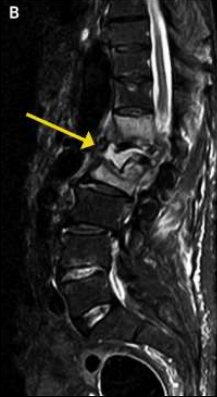

term image

Hiperintensos